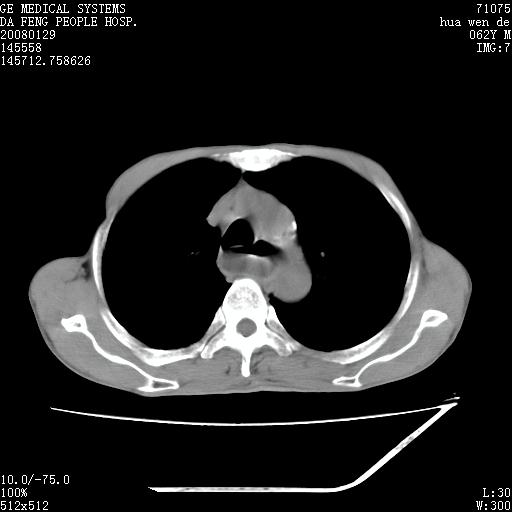

男性,67岁。作肺部检查时发现

胸腔胃不支持,

因无病史,暂考虑:贲门失驰缓症并肺部化脓感染(吸入性)

胸腔胃多伴有左侧胸膜术后改变~!!请提供病史!!

食管全程扩张,壁均匀不厚,喷门失弛缓症

右上肺空洞可见液平,临近肺野磨玻璃密度,考虑1.结核2.脓肿

贲门失驰缓症.肺部感染伴脓肿形成。支持!是否吸入性要结合临床诊断,我们影像是看不出来的。但胸腔胃能排除(1.没有手术史支持,2.双侧胸廓对称,胸壁、肋骨及胸膜规整,3,食管壁明显扩张内壁光滑,胸腔胃黏膜皱襞多较厚)。

贲门失驰缓症.(硬皮病?)肺部感染考虑结核